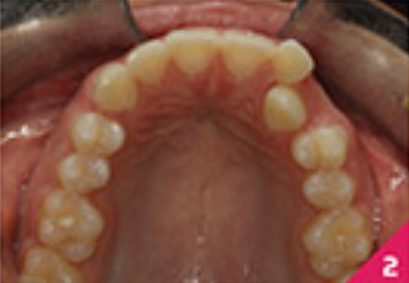

Праве ікло верхньої щелепи було в перехресному перекритті, а різці верхньої і нижньої щелепи були нахилені. Скупчення зубів було помірним у верхньому зубному ряді та легким у нижньому.

На фото зображено розташування зубів перед початком лікування.